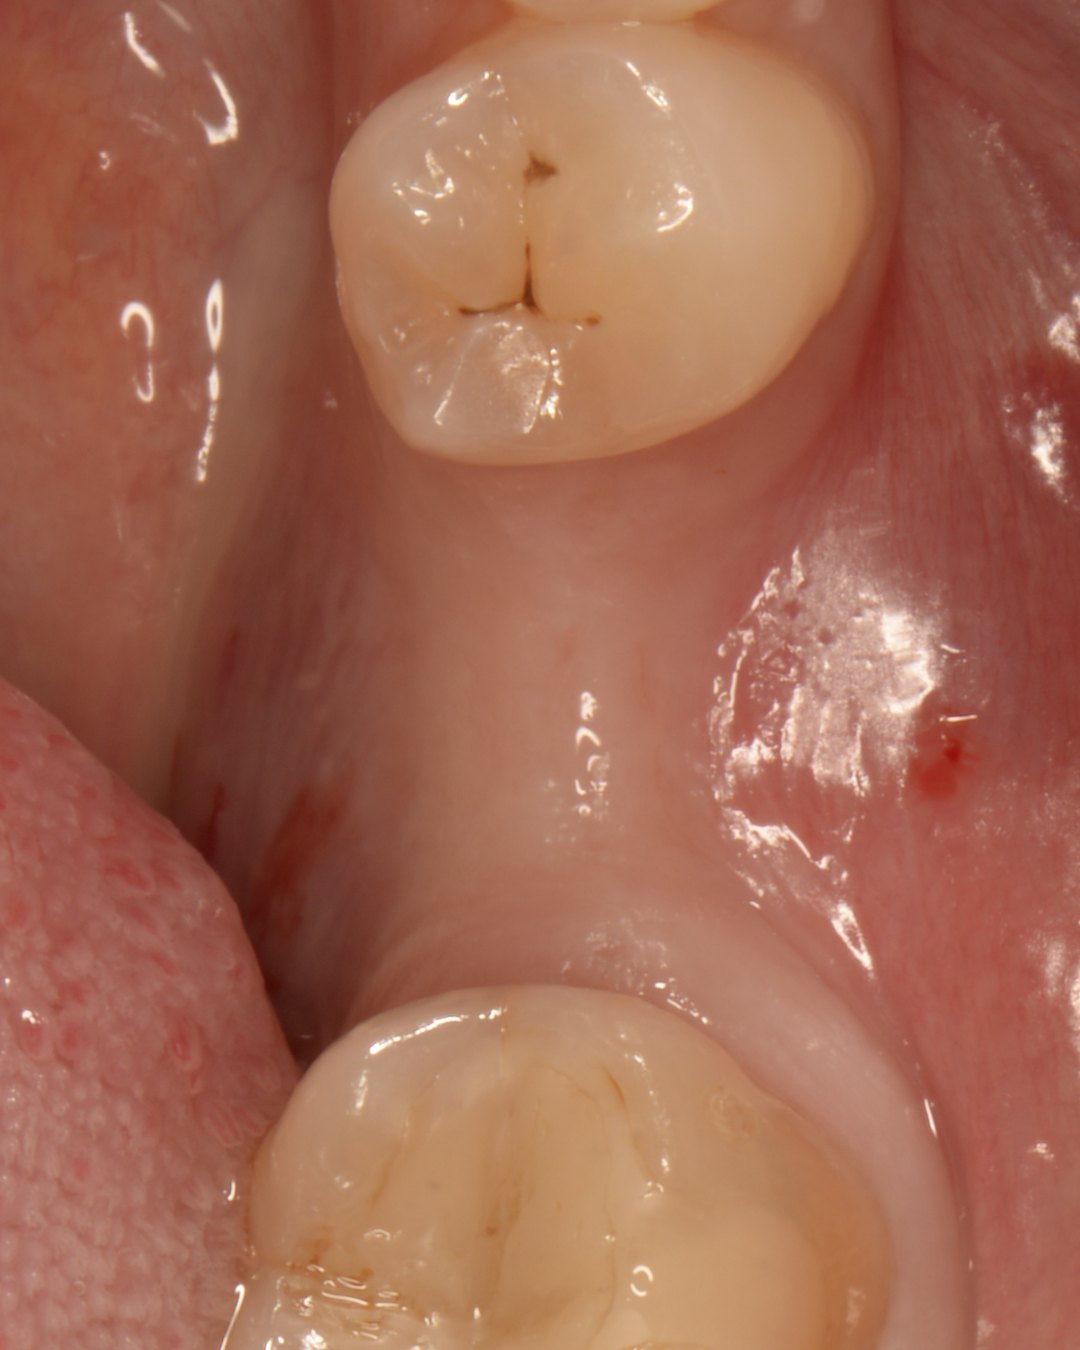

Складна негайна імплантація з кістковою пластикою

Олена, 30 років

Запальний процес у ділянці зуба внаслідок ускладненого карієсу та інфекції в кореневих каналах після перелікування. Значний дефект кісткової тканини з формуванням кістозного ураження та сполученням із гайморовою пазухою, що ускладнювало можливість негайної імплантації.